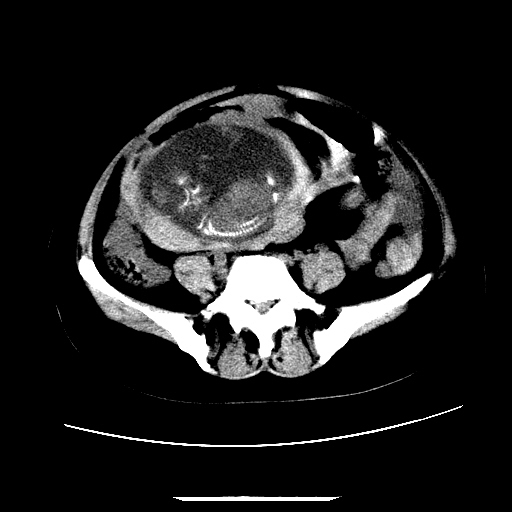

f,45y.怀孕4月晕倒,b超提示死胎,有手术结果,请展开讨论后明天告诉。

膈下-肠间隙内见气体密度影,子宫轮廓显示不清,宫腔-腹腔积液,首选考虑---子宫破裂出血。

1)宫腔妊娠。2)子宫破裂出血,腹腔及盆腔积血。

感谢同行们的高见。手术结果:子宫破裂出血。

我们的诊断是:腹、盆腔积液(考虑腹盆腔脏器破裂出血);宫腔妊娠。让人纳闷的是当时我们没有经验,现在回头看看分析:4月宫腔妊娠:1、洋膜囊不可能紧贴胎体这么小;2仔细看看子宫后壁肌层模糊不清;3腹、盆腔液体来源原因?4、45岁高龄妊娠有晕倒。由此可大胆诊断:宫腔妊娠子宫破裂出血。